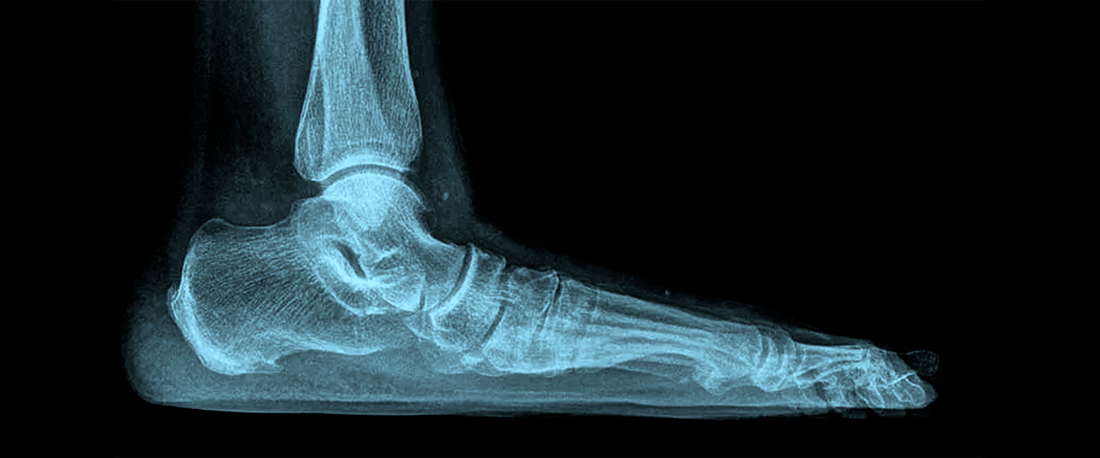

What Are Flat Feet?

Flat feet (also known as fallen arches) occur when the arches of the feet collapse, causing the entire sole to make full contact with the ground. Some people are born with flat feet, while others develop them due to age, injury, or medical conditions.